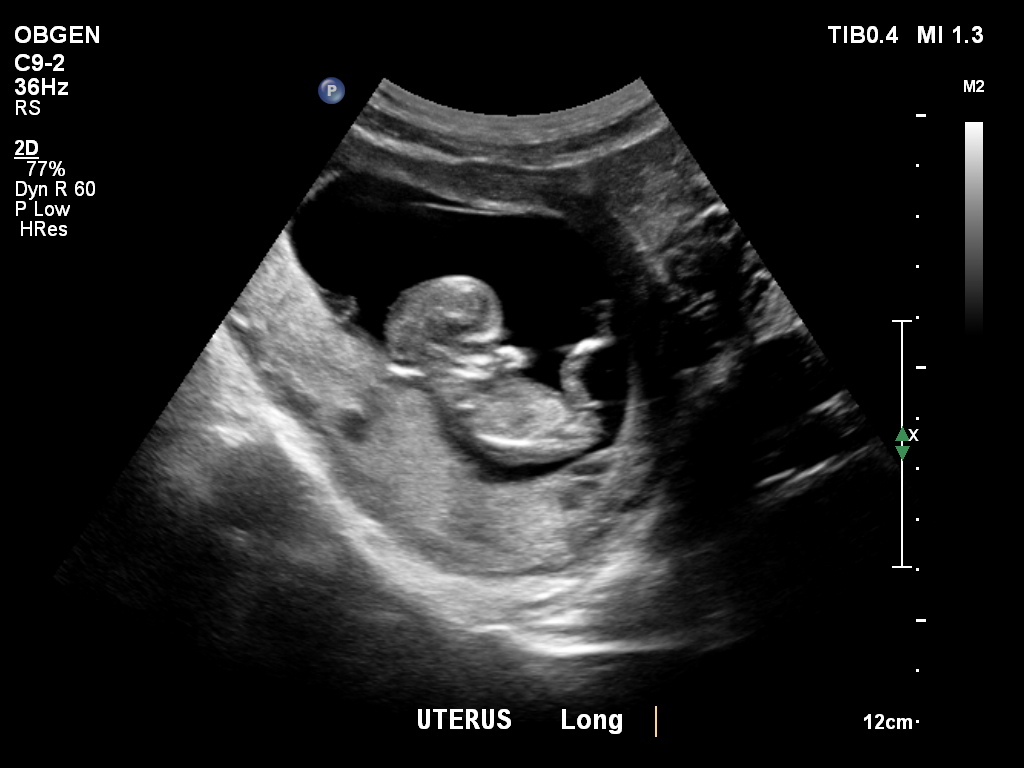

12 week 4 day scan and baby measuring 11 weeks 5 days. I'm thinking baby girl but I would love your opinions!! :DAttachment 24669